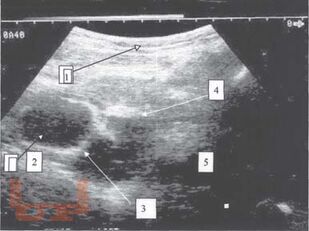

Томографическая диагностика опухолей и опухолевидных образований яичника у девочек

Диагностика и лечение опухолей и опухолевидных образований яичников у девочек и подростков является актуальной проблемой. Совершенство методов диагностики при данной патологии, хорошо зарекомендовавших себя во многих областях медицины, способствует внедрению их в клинику детской гинекологии, онкогематологии, детской хирургии.

Разнообразие средств диагностики, отличающихся по физическим данным и разрешающим способностям, а также по стоимости аппаратуры и самих исследований, часто ставит врача перед сложной проблемой определения необходимого минимума применяемых методов, последовательностью их выполнения и интегрирования результатов разных исследований в единую диагностическую концепцию.